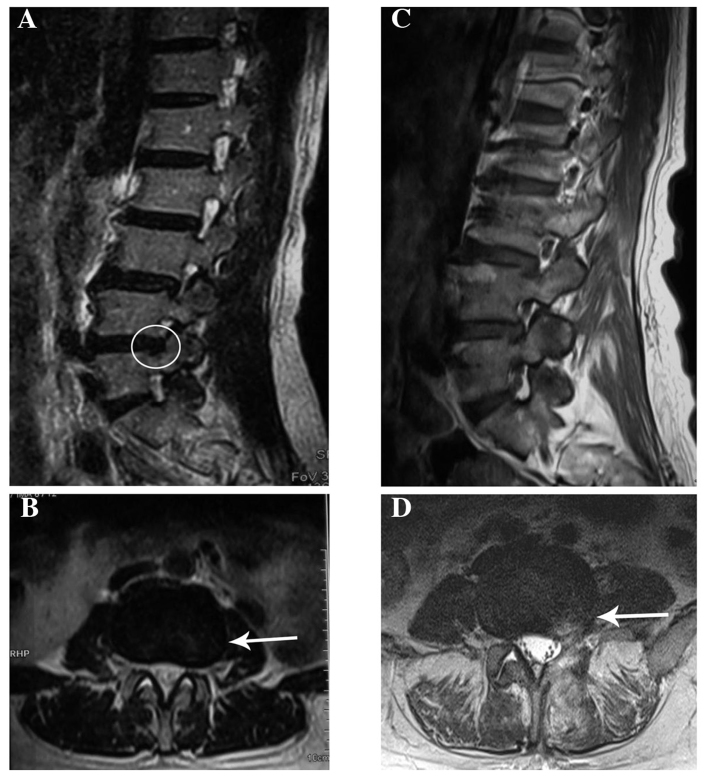

A 46-year old woman was admitted to another hospital with a 3-month history of pain that radiated from the posterior aspect of the left thigh to the lateral aspect of the leg and left foot, and was associated with numbness of the left lower limb. The patient had undergone a lumbar magnetic resonance imaging (MRI) examination, which revealed a mild L4/5 intervertebral disk herniation (Fig. 1A and B). A clinical diagnosis of intervertebral disk herniation was made, and L4/5 discectomy was performed (Fig. 1C and D). However, there was little symptomatic improvement after 2 months. The patient was subsequently referred to our institution.

Figure 1.

(A) T2-weighted sagittal view prior to L4/5 discectomy showing a left disc herniation at the L4-5 level with compression of the nerve root (circle). (B) T2-weighted axial view prior to L4/5 discectomy showing left lateral disc herniation at the L4-5 level (arrow). (C) T2-weighted sagittal view following L4/5 discectomy. (D) T2-weighted axial view showing high T2 signal of the surgical scar (arrow).